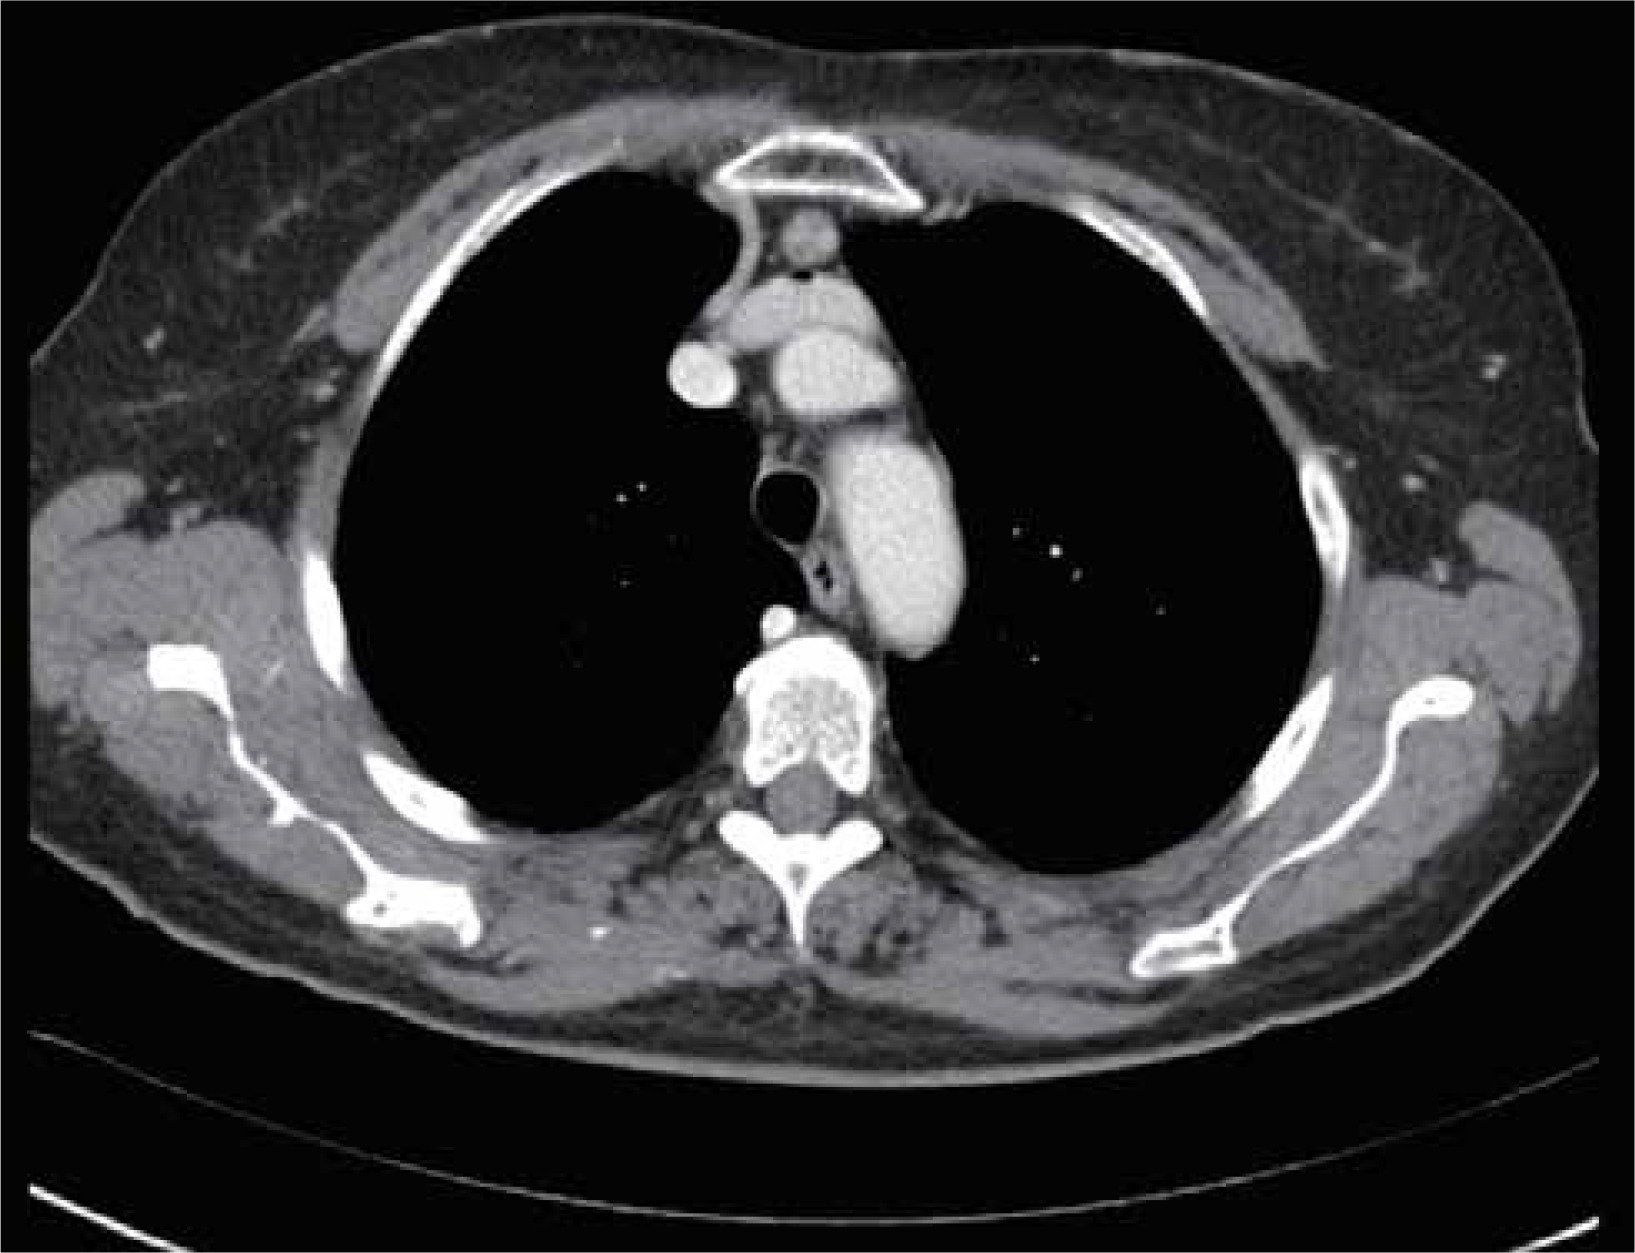

In addition, a contrast-enhanced computed tomography chest scan must be performed on all subjects for evaluation (Figure 2). PET-CT and/or magnetic resonance scan can also be conducted in the case of thymoma suspicion or to differentiate a small thymoma from thymic hyperplasia. Pre-operative X-rays of the chest must be carried out to check for extensive adhesions symptoms associated with the thoracic surgical operation or prior pleuritis, which might make a robotic approach impossible. Electrocardiogram, full examination of blood and pulmonary function tests must all be included in the functional evaluation.